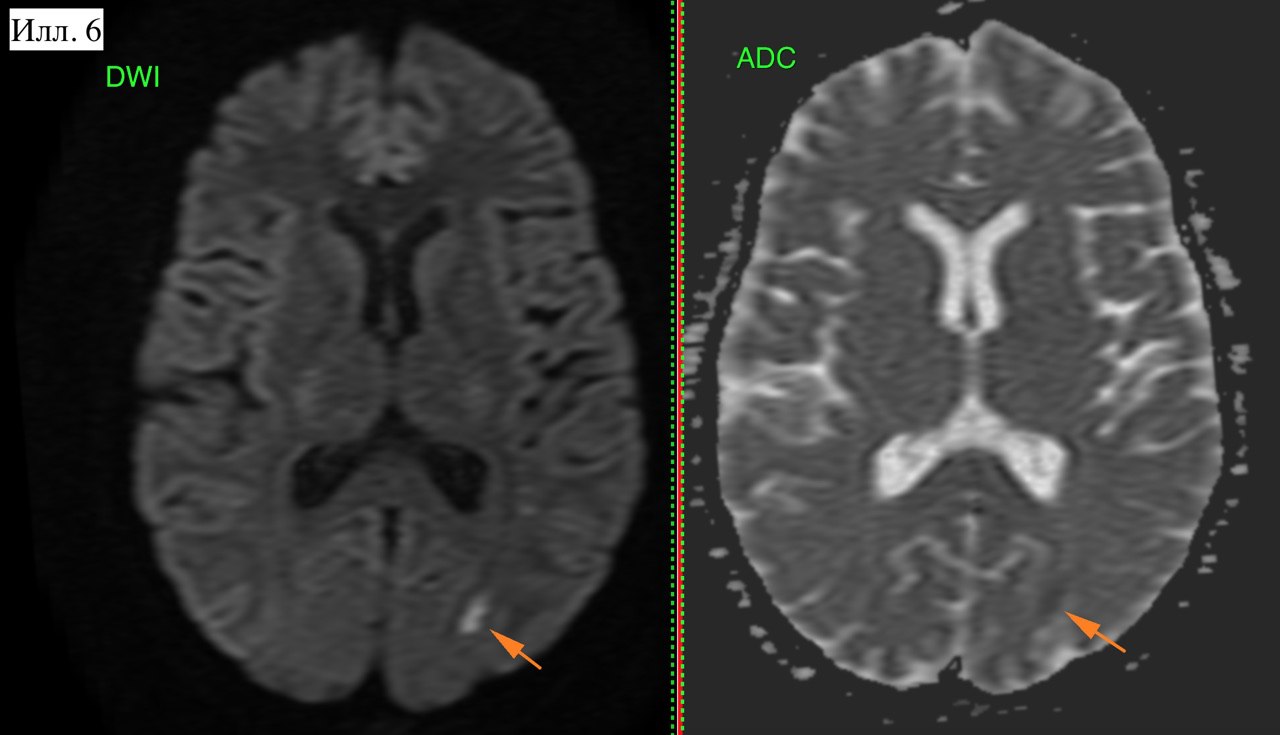

Илл. 6. Стрелкой указан очаг цитотоксического отека: высокий сигнал на DWI и низкий на ADC. Т.е. очаг острого ишемического инсульта